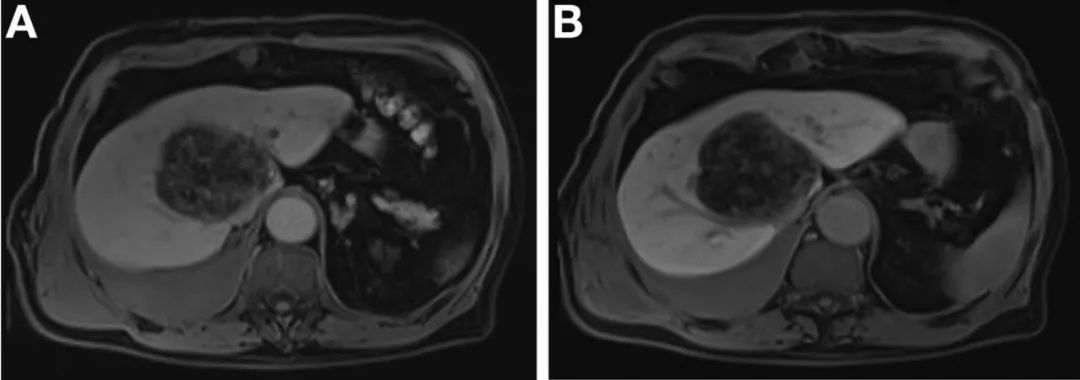

腹部MRI显示左肝叶有7 x 7.5 x 7.2 cm单发的异质性病变,主要为脂肪病变,累及右肝叶(图A和B)。